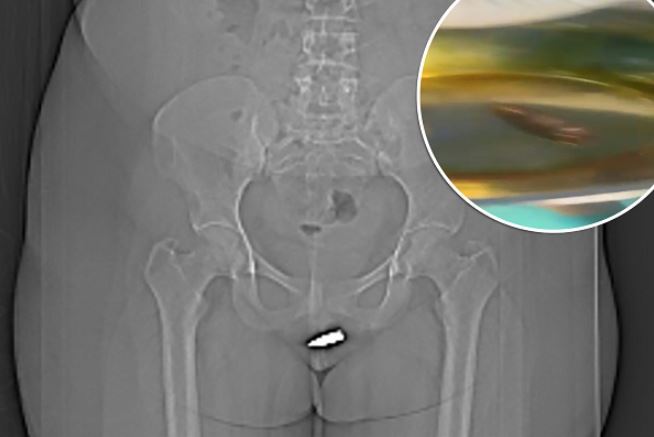

Pelvic exams showed where the bullet had penetrated the clitoris, while CT scans confirmed the placement of the bullet.

CT scans revealed the bullet had become lodged inside her clitoris after being fired into her vulva, meaning she required surgery to have it safely removed.

Under local anaesthetic, medics then proceeded to remove the bullet from the clitoris.